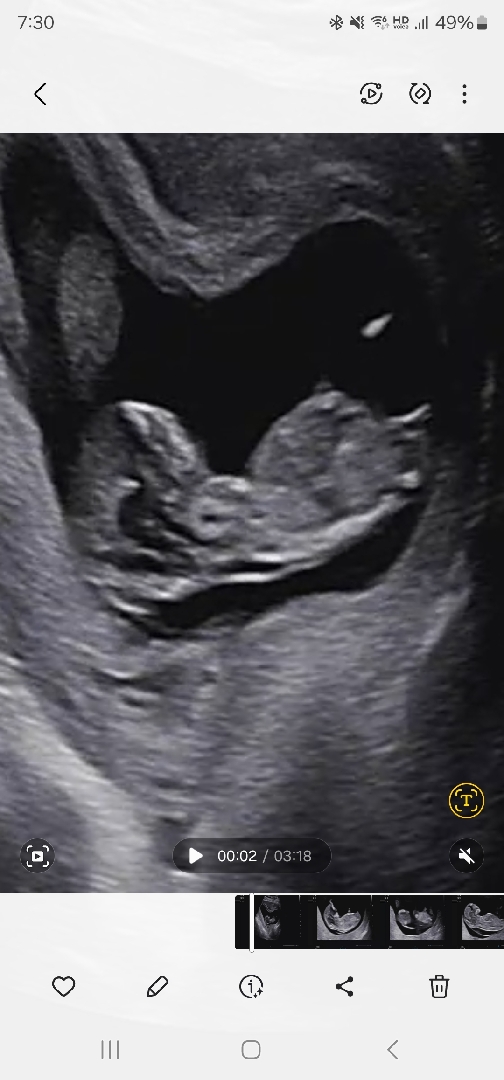

각도법 한번만 봐주세요~~

12주에요! 성별 상관 없지만 궁금해가지고..ㅎㅎ 부탁드려요~~